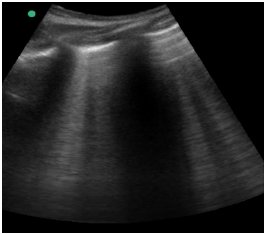

Um paciente de 40 anos de idade, vítima de queda de 9 metros (estava trabalhando quando o telhado cedeu), trazido à sala vermelha pelo SAMU, foi admitido com PA = 80 mmHg x 40 mmHg, FC = 120 bpm e tempo de enchimento capilar = 4 segundos. O emergencista procedeu ao e-fast, que evidenciou o achado apresentado na imagem.

Hemitórax direito superior

Enunciado 4334998-2

Hemitórax esquerdo superior

Enunciado 4334998-3

Insonação cardíaca Janela apical 5 câmaras com VTI de 9,08 cm

Enunciado 4334998-4

O nefrologista foi chamado a opinar na melhor conduta para o paciente. Para tanto, realizou uma ultrassonografia beira leito pulmonar e mensurou a velocidade integral tempo (VTI) do trato de saída do ventrículo esquerdo. Chegou, assim, à conclusão que poderia ser feita uma expansão no paciente. Com base nas imagens apresentadas, é correto afirmar que conduta recomendada pelo nefrologista está

Enunciado 4334997-1

No segundo dia da admissão, o paciente evoluiu com CPK de 20.000, diminuição de diurese, elevação dos níveis de ureia e creatinina, sendo aventada a hipótese de rabdomiólise. Diante disso, assinale a alternativa que corresponde à conduta mais assertiva a ser adotada, no caso.

Enunciado 4334996-1

A melhor conduta do emergencista nesse momento é